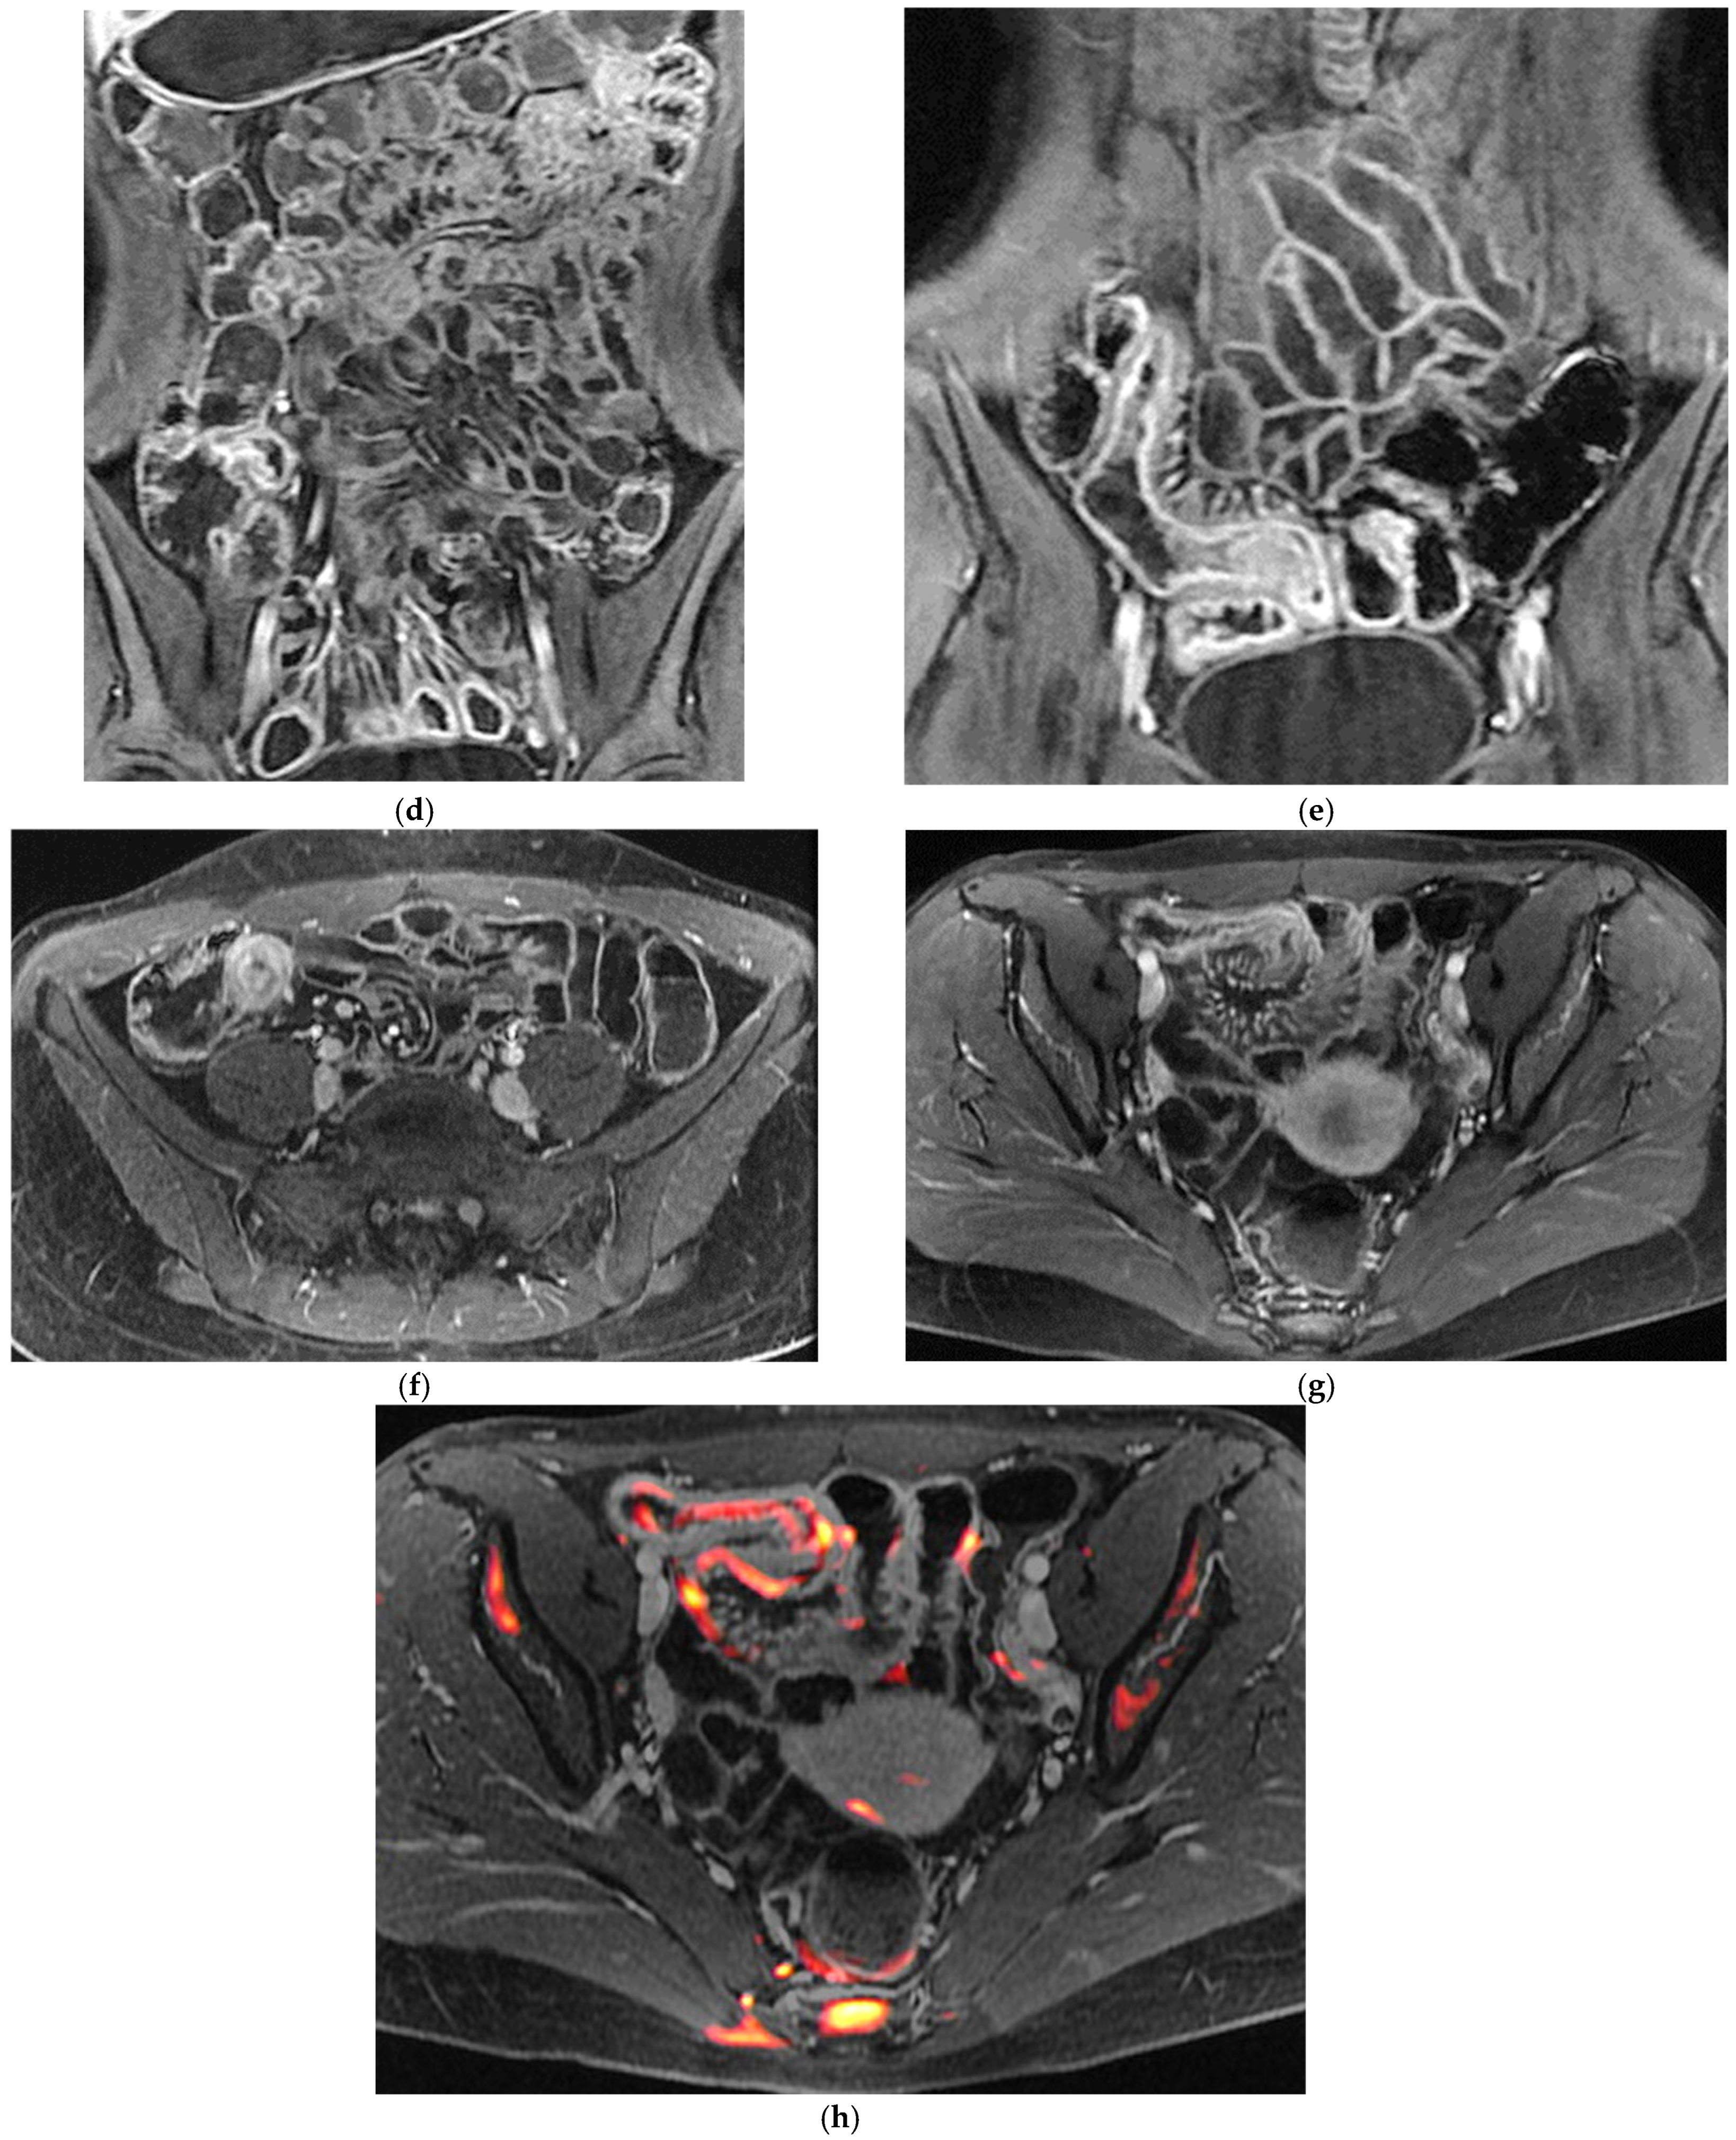

5. Perianal Crohn’s Disease: The Role of MRI and Complementary Techniques

Perianal involvement represents one of the most debilitating manifestations of Crohn’s disease, with a substantial impact on quality of life and long-term prognosis. Fistulas and abscesses in this region are frequently complex, may be recurrent, and often coexist with active luminal disease. Because physical examination is limited in its ability to define the full extent and configuration of fistulous tracts, cross-sectional imaging, particularly MRI, has become indispensable in both baseline assessment and longitudinal follow-up [42,43].

MRI is widely regarded as the gold standard imaging modality for perianal Crohn’s disease, owing to its exquisite soft-tissue contrast and multiplanar capabilities. A typical MRI protocol for perianal fistulas includes high-resolution T2-weighted sequences with and without fat suppression in axial, coronal, and often oblique planes aligned with the anal canal, together with T1-weighted images before and after gadolinium administration. Fat-suppressed post-contrast images are particularly helpful in delineating enhancing fistula tracts and active inflammatory components, while T2-weighted sequences excel at highlighting fluid-rich collections and oedematous tissues. Many centres increasingly add diffusion-weighted imaging (DWI), which may further characterize inflammatory activity and help differentiate between active tracts and more quiescent fibrotic tissue [42,43,44,45,46,47,48,49,50,51].

From a morphological perspective, MRI enables precise classification of fistulas according to established schemes (e.g., Parks’ classification), distinguishing intersphincteric, trans-sphincteric, supra-sphincteric, and extrasphincteric trajectories, as well as identifying secondary extensions and supralevator involvement. This detailed anatomical mapping is fundamental for surgical planning, including the placement of setons, the choice and timing of sphincter-sparing procedures, and the assessment of potential risks to continence. MRI is also highly sensitive for detecting associated abscesses, which may be small, deeply located, and clinically occult. Identifying these collections before initiating or intensifying immunosuppressive therapy is critical to avoid sepsis and treatment failure [42,43,44,45,46,47,48,49,50,51].

The van Assche MRI score, introduced in the early 2000s, was a landmark attempt to quantify perianal disease severity by integrating features such as the number and location of fistula tracts, degree of extension, presence of abscesses, and T2-weighted signal characteristics [47,48]. Although its routine use in everyday practice is variable, the score has been widely adopted in clinical trials and longitudinal studies as a structured way to monitor response to therapies such as anti-TNF agents (Table 5). Subsequent work has proposed modified versions of the van Assche index and alternative MRI-based scoring systems, aiming to improve sensitivity to change and to correlate more closely with clinical and patient-reported outcomes [49]. A significant recent advancement is the MAGNIFI-CD index, a novel MRI-based scoring system specifically designed to refine the evaluation of perianal fistulizing Crohn’s disease by integrating both morphological and inflammatory biomarkers into a unified framework [50]. The MAGNIFI-CD score systematically quantifies active inflammatory features—including mural and perilesional enhancement patterns, diffusion-weighted imaging characteristics, and the presence of inflammatory oedema—alongside established structural descriptors (Table 5). Early validation studies suggest that the MIGNIFI-CD index demonstrates superior sensitivity to change compared with traditional scoring systems and may better predict clinically meaningful outcomes, such as fistula healing or persistence of occult activity despite apparent clinical remission. By incorporating a broader range of MRI parameters and emphasising functional imaging markers, the MIGNIFI-CD index represents a promising tool for standardising radiologic assessment in both routine practice and clinical research, particularly within treat-to-target strategies [51].

Table 5.

MRI plays a crucial role in the evaluation of treatment response in perianal Crohn’s disease. Clinical closure of external openings does not necessarily equate to radiologic healing, as residual active tracts or small collections may persist despite apparently satisfactory external findings. Longitudinal MRI studies have demonstrated that, in patients treated with biologic therapies, perianal fistula tracts often decrease in caliber and contrast enhancement before undergoing complete fibrosis. Persistent T2 hyperintensity or ongoing contrast enhancement has been shown to predict disease relapse, even in the absence of overt clinical drainage [43,44,45,46,47,48,49,50,51]. For this reason, MRI is increasingly being integrated into treat-to-target strategies for perianal Crohn’s disease, with radiological improvement or healing recognized as a key therapeutic endpoint alongside clinical remission.

Other imaging modalities can complement MRI in selected situations. Endoanal ultrasound (EAUS) offers excellent spatial resolution near the anal canal and can be particularly useful in preoperative evaluation of sphincter integrity; however, its field of view is limited and it is less effective for complex or high fistulas. It also requires deep sedation in the presence of inflammatory perianal involvement. CT, by contrast, is generally reserved for acute presentations with suspected pelvic abscesses, sepsis, or other complications but it is clearly inferior to MRI for detailed fistula mapping and is avoided for repeated follow-up because of radiation exposure [51].

In summary, MRI has become the cornerstone of perianal Crohn’s disease imaging. It provides an unparalleled combination of anatomical detail, functional information, and reproducible scoring systems that together guide both medical and surgical decision-making. The integration of MRI findings with clinical assessment, endoscopy, and biomarkers is essential for a truly comprehensive evaluation of this particularly challenging phenotype of Crohn’s disease.